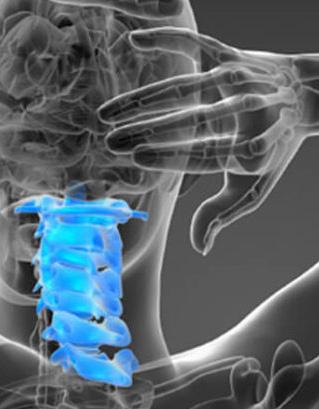

TOTAL DISC REPLACEMENT? TOTAL DISC

Total disc replacement (TDR) may be an alternative to spinal fusion for patients with cervical or lumbar herniated discs or degenerative disc disease.

The goals of total disc replacement surgery are to maintain segmental spinal motion, relieve pain, increase activity, restore disc height and proper spine curvature, and reduce post-operative recuperation time.

If you are experiencing neck or back pain and are considering surgery, isn't it worth your time to schedule an appointment with Dr. Jason E. Garber to nd out if motion preservation technology is an option for you?

Dr. Garber is one of Southern Nevada's most experienced spinal surgeons and a leader in arti cial disc replacement surgery.